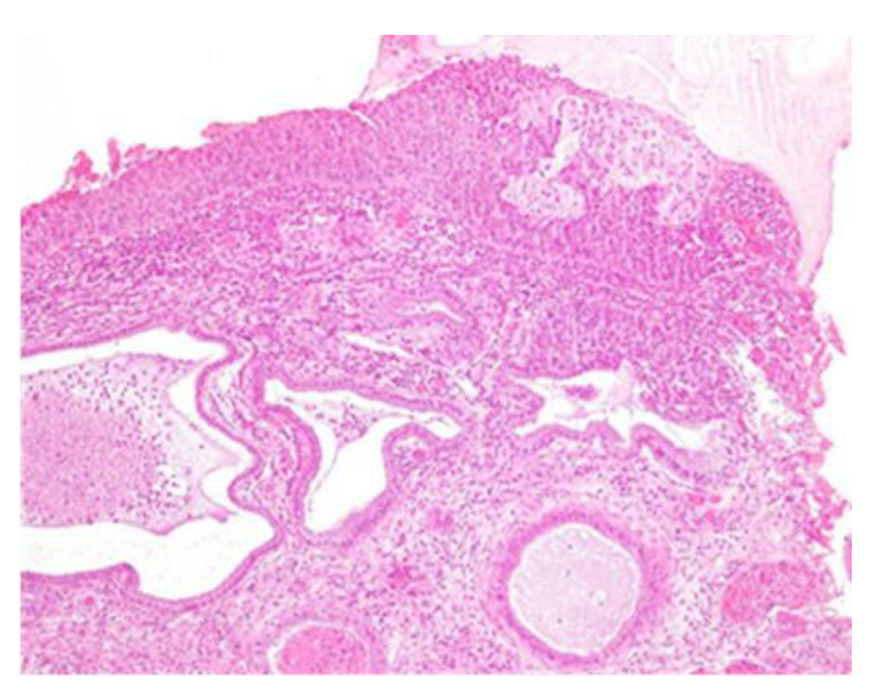

Figure 4.

CIN3 histological sample of the left enlargement margin; also, in this case, enlarged and hyperchromatic nuclei, clumped chromatin, irregularities and indentations in the nuclear membrane, and an altered nuclear/cytoplasmic ratio are observed.